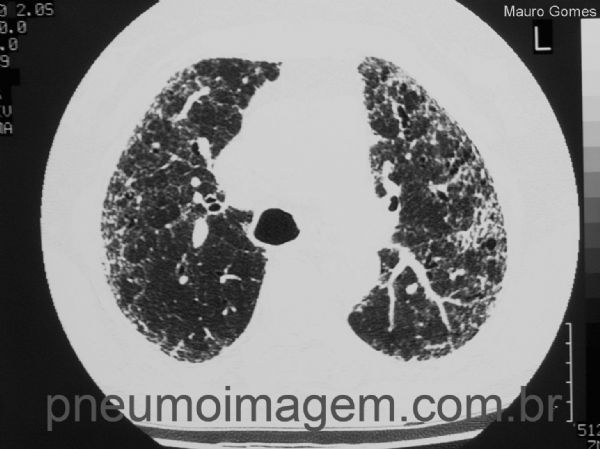

Os achados na TCAR variam desde dano alveolar difuso a até BOOP ou PINE (pneumonia intersticial não específica). Neste corte observamos áreas em vidro fosco de predomínio periférico com opacidades reticulares e faveolamento menos intenso que na fibrose pulmonar idiopática.

The HRCT findings of pulmonary lesions from amiodarone range from diffuse alveolar damage to BOOP or NSIP (non-specific interstitial pneumonia). In this CT slice we observe areas of ground glass of peripheral predominance with reticular opacities and less intense honeycombing than in idiopathic pulmonary fibrosis.